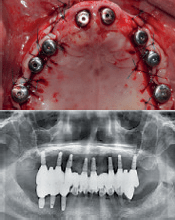

Neposredna ugradnja implantata izvedena je u području gornjih centralnih sjekutića, a svih osam AnyRidge implantata postavljeno je korištenjem jednofaznog hirurškog zahvata. Tada je korištena kombinacija implantata s konvencionalnom RBM površinom (RBM- površina obrađena resorptivnim abrazivnim medijem) i implantata s XPEED površinom.